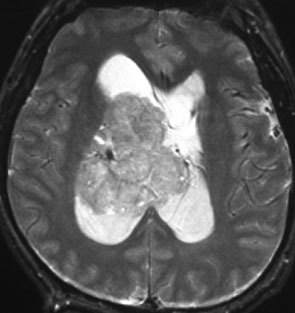

central neurocytomaは腫瘍実質部分が多いものです。しかし,この例のように腫瘍の大部分をのう胞が占める症例もあります。

anterior transcallosal apprroachで亜全摘出しました。20代の女性でしたが,その後,子どもも生まれて元気です。

腫瘍の位置から,透明中核が発生母地であることが推測されます。central neurocytomaは,惻脳室壁にべとべとくっつくので,脳質上衣からの剥離は簡単ではありません。鑑別しなければならないのが,成人の毛様細胞性星細胞腫ですが,この症例では決定的な鑑別点はないでしょう。のう胞性の毛様細胞性星細胞腫と同様に,腫瘍の増殖力は低く無理して全摘出するものではありません。